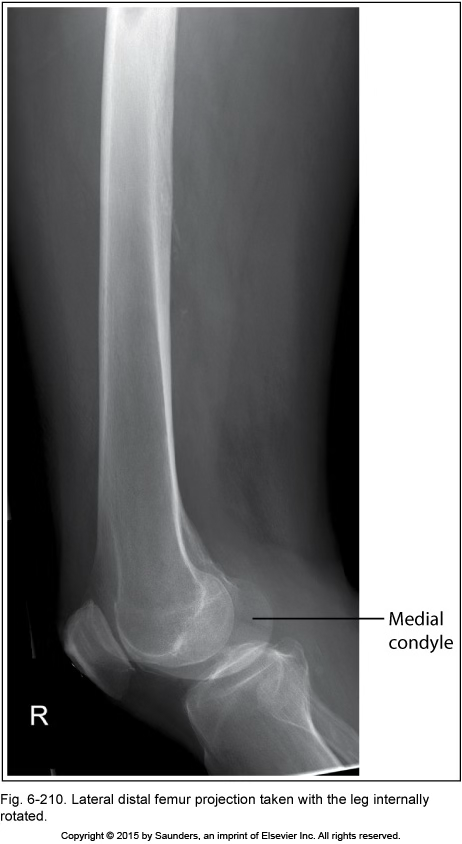

lateral femur

leg internally rotated